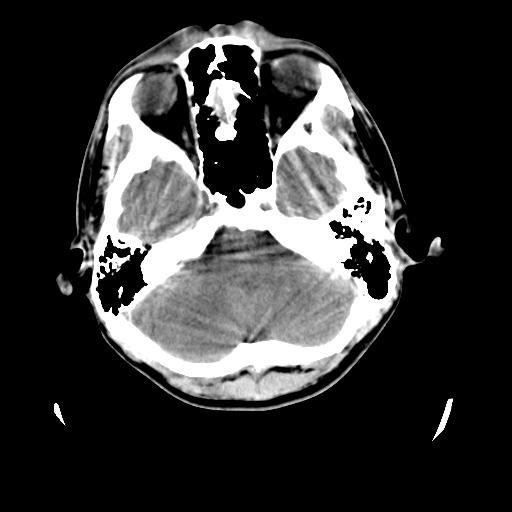

标题: CT23601:男, 17岁,剧烈头痛一小时。 [打印本页]

标题: CT23601:男, 17岁,剧烈头痛一小时。

男, 17岁,剧烈头痛一小时。

颅脑ct轴位平扫颅内未见明确异常;建议:必要时复查。

颅脑ct平扫颅内未见明确异常;剧烈头痛,建议必要时dsa造影。